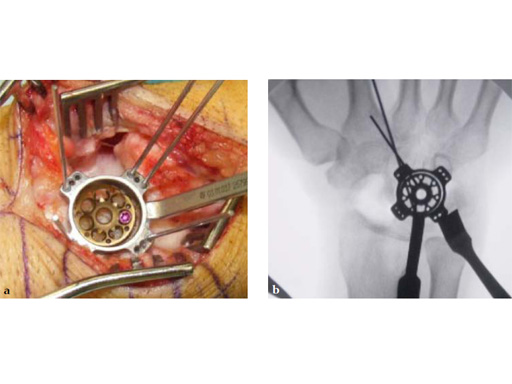

Fig 3ab Bone debridement. Guide positioning and fixation.

Fig 3c Bone debridement. Guide positioning and fixation.

Fig 4c Once the carpal junctions have been putting closer by the new reduction-compression guide, reaming is done.

Fig 5ab Plate positioning and fixation. The combined VA-locking-standard guide allows drilling in the appropriate direction.